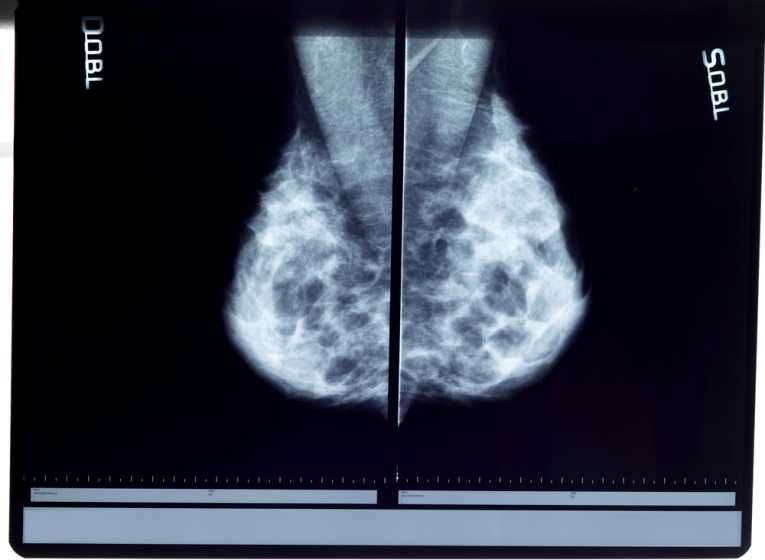

These days, all over the world and in the United States in particular, breast cancer is one of the most common health risks for women. It's not something to be taken lightly - this disease is a killer, and more often than not it has long-term consequences even for those that survive it. So it's not strange that scientists have devoted a lot of time and effort to understand breast cancer, and all that research has turned out to be very productive; for one, we have been able to identify substantial risk factors for the disease such as aging, timing of menopause and first menstruation, specific genetic characteristics, and so on.

Now, the Institute of Medicine at Washington, D.C. has reviewed multiple scientific studies in order to produce a comprehensive report on the potential relationship between environmental factors and the risk of breast cancer.